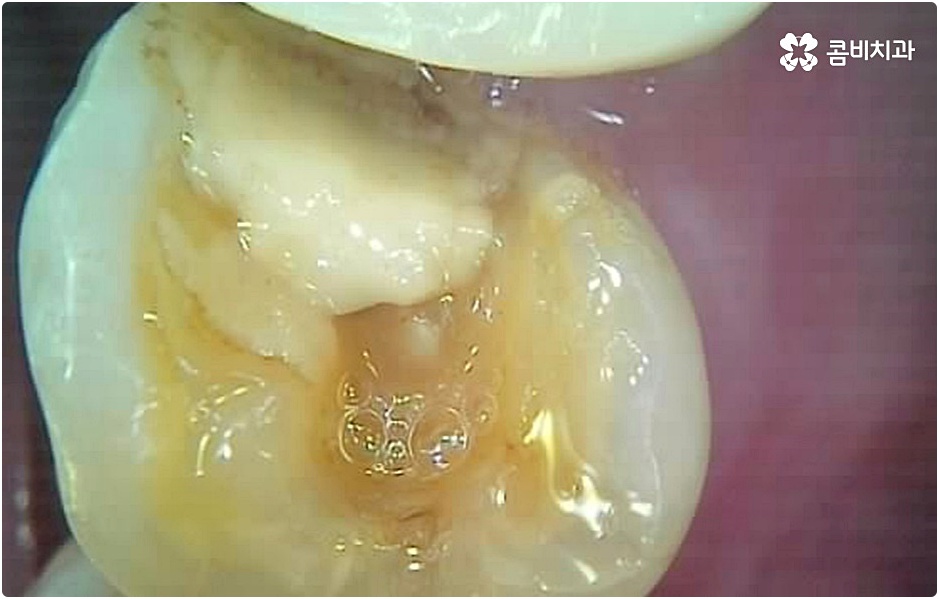

그러나 언급했던 것처럼 잇몸뼈 상태에 대해서 먼저 체크해 봐야 하기 때문에 누구나 받을 수 있는 치료 과정은 아니라는 점을 분명히 알아두실 필요가 있습니다. 이렇게 잇몸뼈를 보충해야 하는 상황 뿐 아니라 충치 또는 치주 질환을 먼저 깨끗하게 치료해야 하는 상황, 상악동까지의 거리가 너무 짧아서 거상술을 통해 혹시 모를 천공과 염증을 방지해야 하는 상황 등 여러 가지 선치료가 필요한 케이스들이 있을 수 있기 때문에 먼저 환자분들의 상황을 자세하게 파악하기 위해서 꼼꼼한 검진을 해 볼 필요가 있으므로 3D CT 등 정밀 검진 장비 보유 여부가 필수적이라고 말씀드린 거예요.

그러나 치아가 빠진 후부터 잇몸뼈는 수축을 하기 시작하기 때문에 오랜 기간 그대로 방치를 하게 되면 잇몸이 내려앉아 주변 치아가 쓰러지고 치열이 흩뜨러지며 악관절까지 좋지 않은 영향을 받게 되는 등 구강 내부적으로 문제가 더 커질 수 있으며, 치아가 크게 부러진 뒤 치근이 일부 남아 있는 상황이라고 하더라도 기능을 전혀 하지 못하여 주변 치아와 잇몸에 지속적인 부담을 주고 있거나 해당 부위를 통해 감염이 일어날 가능성이 높다면 이를 발치하고 빠르게 기능적 심미적 대체를 해 줄 필요가 있으니 될 수 있는대로 바로 치과로 내원하셔서 검진부터 꼼꼼하게 받아보시고 그에 적합한 치료를 받으시길 권유드리고 있어요.

환자분들의 상황에 따라 즉시 임플란트 시술이 가능하지 않은 경우라고 해도 만약 본원과 같이 치과 내부에 자체 기공소를 갖추고 있다면 기간 단축은 물론이고 보다 정교하고 섬세한 보철물 제작 및 혹시 모를 수리와 수정 역시 빠르고 원활하게 이루어진다는 점에서 환자분들의 부담과 불편이 크게 줄어들 테니 너무 걱정하실 필요는 없을 거예요. 또한 임플란트 치아의 경우 정기 검진을 꼬박꼬박 받고 스케일링 치료 등을 통해 주변 잇몸 건강을 철저하게 돌본다면 거의 반영구적으로도 사용할 수 있으니 임플란트 시술 후 일상 생활 속에서 이를 건강하게 유지 관리할 수 있도록 식습관 및 생활 습관, 칫솔질 등에 주의하면서 내원 주기를 잘 맞춰주시길 당부드리고 있습니다.